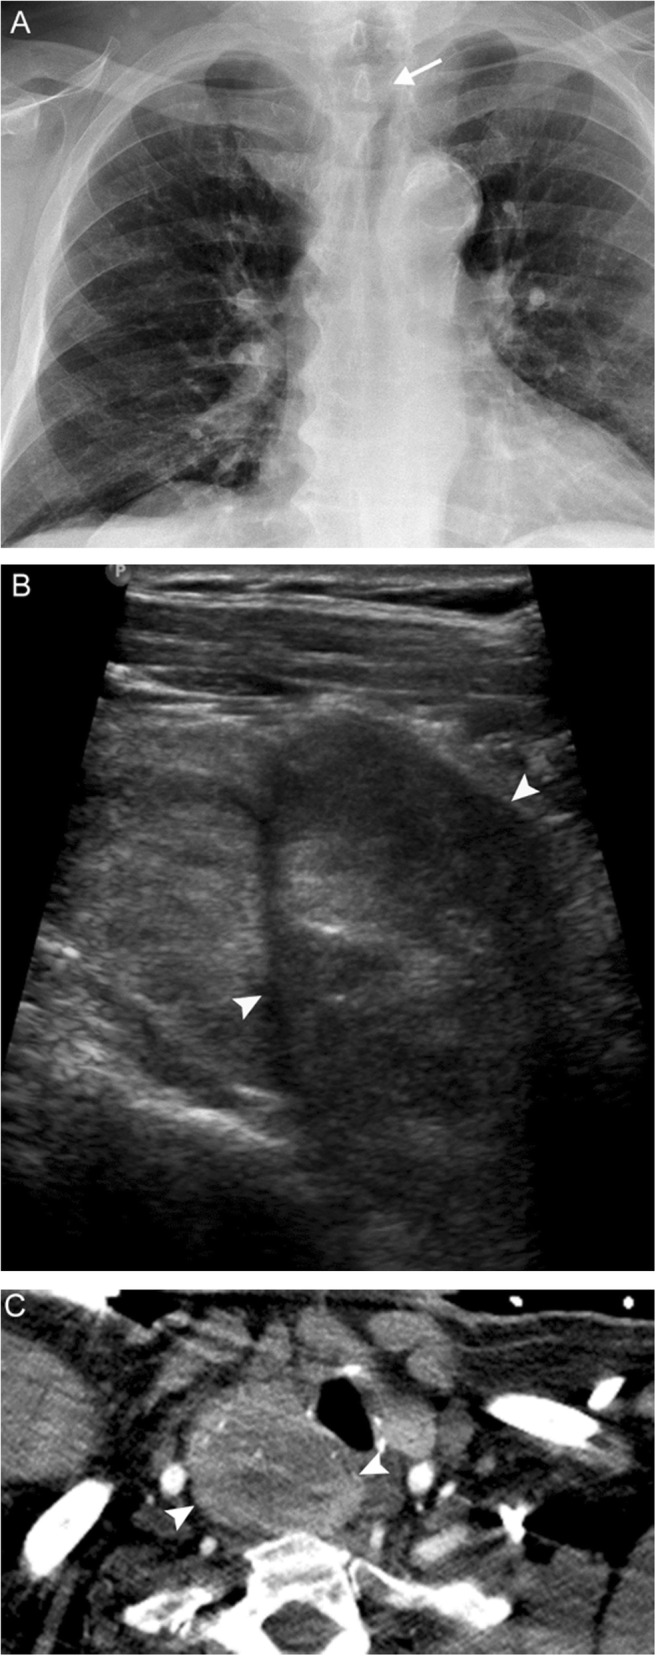

Fig. 18.

Thyroid carcinoma. A 78-year-old man presenting with persistent cough, hoarse voice, and dyspnea. Chest radiograph (a) reveals a right paratracheal mass indenting the subglottic trachea (white arrow). Subsequent neck US (b) and chest CTA (c) reveal a solid heterogenous mass with calcifications (white arrowheads), which narrows but does not invade the glottic/subglottic airway. Fine needle aspiration revealed follicular thyroid carcinoma